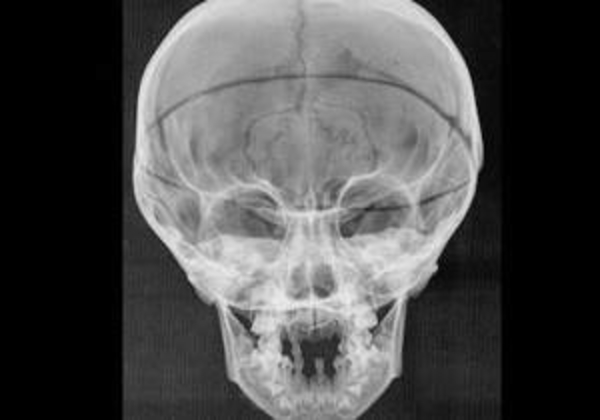

По мнению авторов исследования, дефицит витамина у Медичи был спровоцирован постоянным проживанием в комнатах, практически лишенных света солнца, ношением одежды скрывающей кожу, а также долгим грудным вскармливанием без добавок животной пищи. Признаки искривления черепа (с поправкой на маньеристский характер письма Понтормо, Бронзино и Биццели) можно обнаружить у детей Медичи даже на прижизненных изображениях.